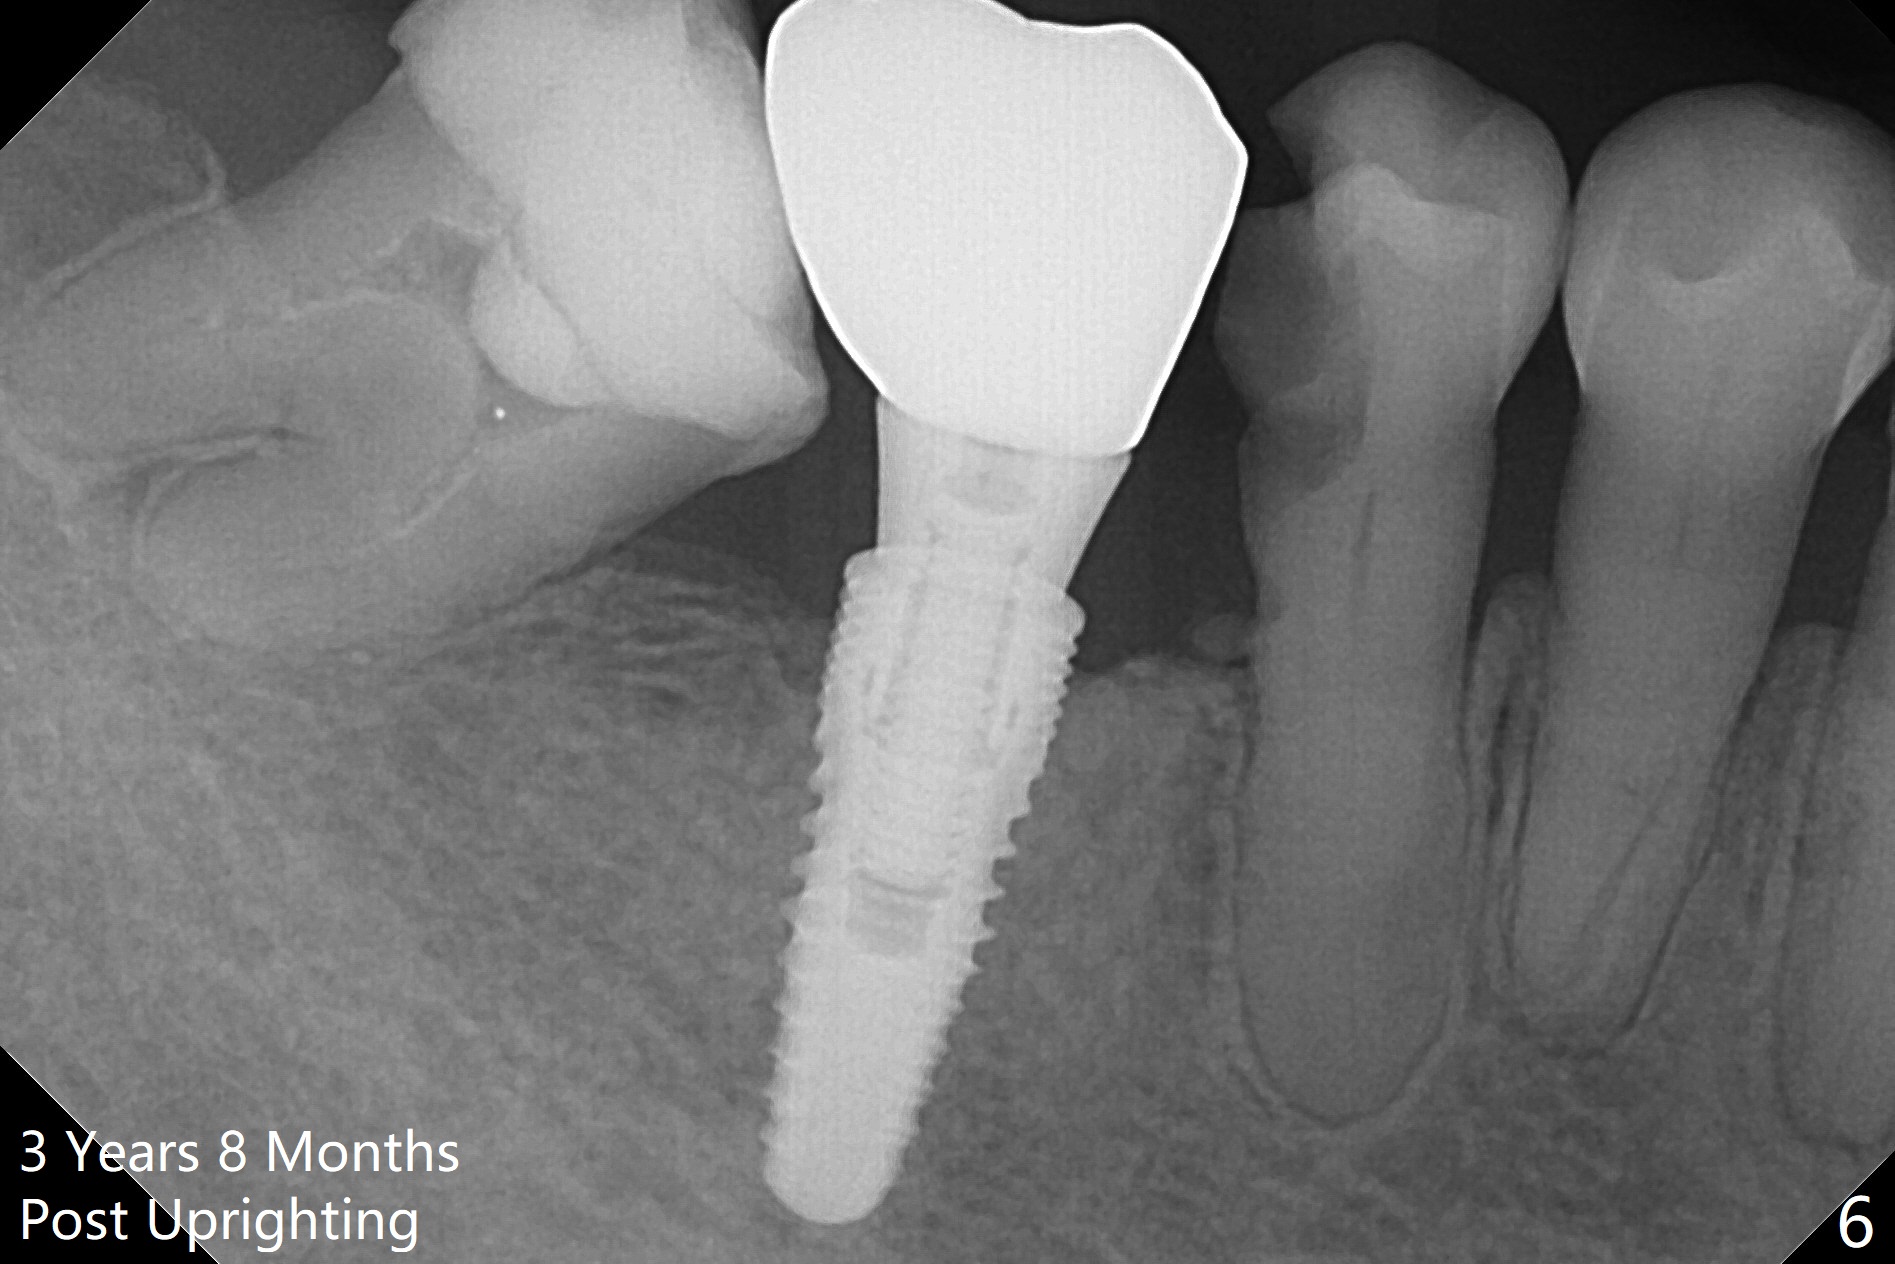

Return to Implant & Ortho 2 Progress Note Anchorage Thread Exposure Last

Xin Wei, DDS, PhD, MS 1st edition 01/12/2018, last revision 02/10/2018